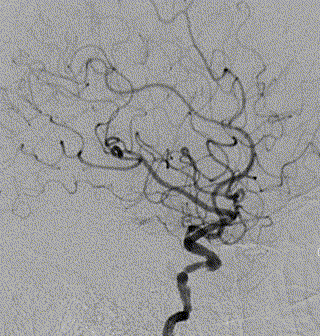

右侧颈动脉造影

左侧颈动脉造影

左侧瘤体形态欠规则,4mm×30mm Streamline 优先处理左侧动脉瘤

术后3月复查,瘤体未见显影,载瘤动脉通畅

同期4mm×20mm Streamline 进一步处理右侧动脉瘤